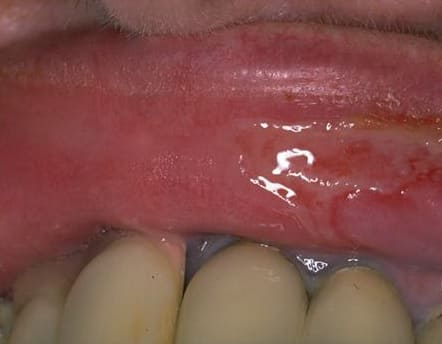

Pemphigus Mucosae = فقاع الاغشية المخاطية